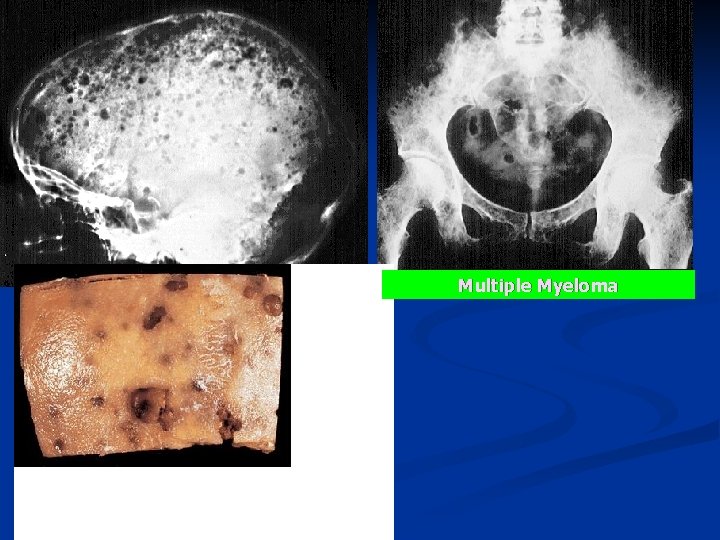

Multiple Myeloma n n Multiple myeloma is a malignant tumor of plasma cells Characterized by n n n n multiple lytic destructive lesions of bone, immunoglobulin abnormalities (monoclonal gammopathy), bone marrow failure, recurrent infections, hypercalcemia, amyloid deposits, renal insufficiency.

n n Over 40 years of age and with an average of 60 years. Multiple myeloma most often involves the vertebral column, ribs, and skull although virtually any, or all, bones can be affected. The most common symptom is bone pain, Other symptoms n n n bone marrow failure (anemia, bleeding), recurrent infections, serum hyperviscosity, hypercalcemia, renal failure of multifactorial pathogenesis (myeloma nephropathy, associated amyloidosis, nephrocalcinosis).

Radiology: Skull, ribs, or other affected bones n Multiple lytic "punched out" lesions. n Osteopenia/Osteoporosis n

Multiple Myeloma